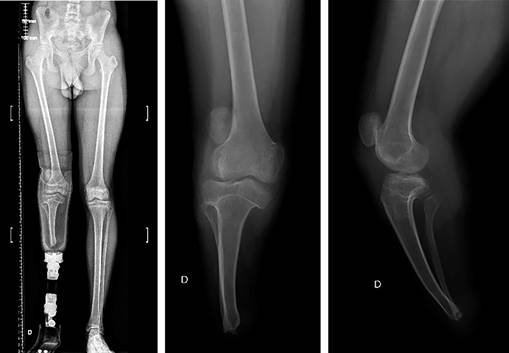

Physical examination revealed knee range of motion from 0o to 90o, altered patellar tracking, quadriceps atrophy, a positive «J» sign, and a highly positive apprehension test. Radiographic examination revealed a high-riding patella with a Caton-Deschamps index of 1.38 (normal range 0.6-1.3) and lateral displacement (Figure 1). Trochlear and tibial plateau dysplasia were observed (Figure 2). Magnetic resonance imaging revealed severe trochlear dysplasia (Dejour type C) and a laterally displaced and tilted patella. The tibial tuberosity-trochlear groove distance (TT-TG) was 18.7 mm on magnetic resonance imaging (MRI).9 The study also indicated elongation of the MPFL and absence of cartilaginous damage. After failed conservative management, involving adaptive adjustments to the prosthesis, a decision was made with the patient to undergo patellofemoral stabilization.

Figure 1: Long leg X-ray film showing limb alignment, and anteroposterior and lateral views of the right knee.